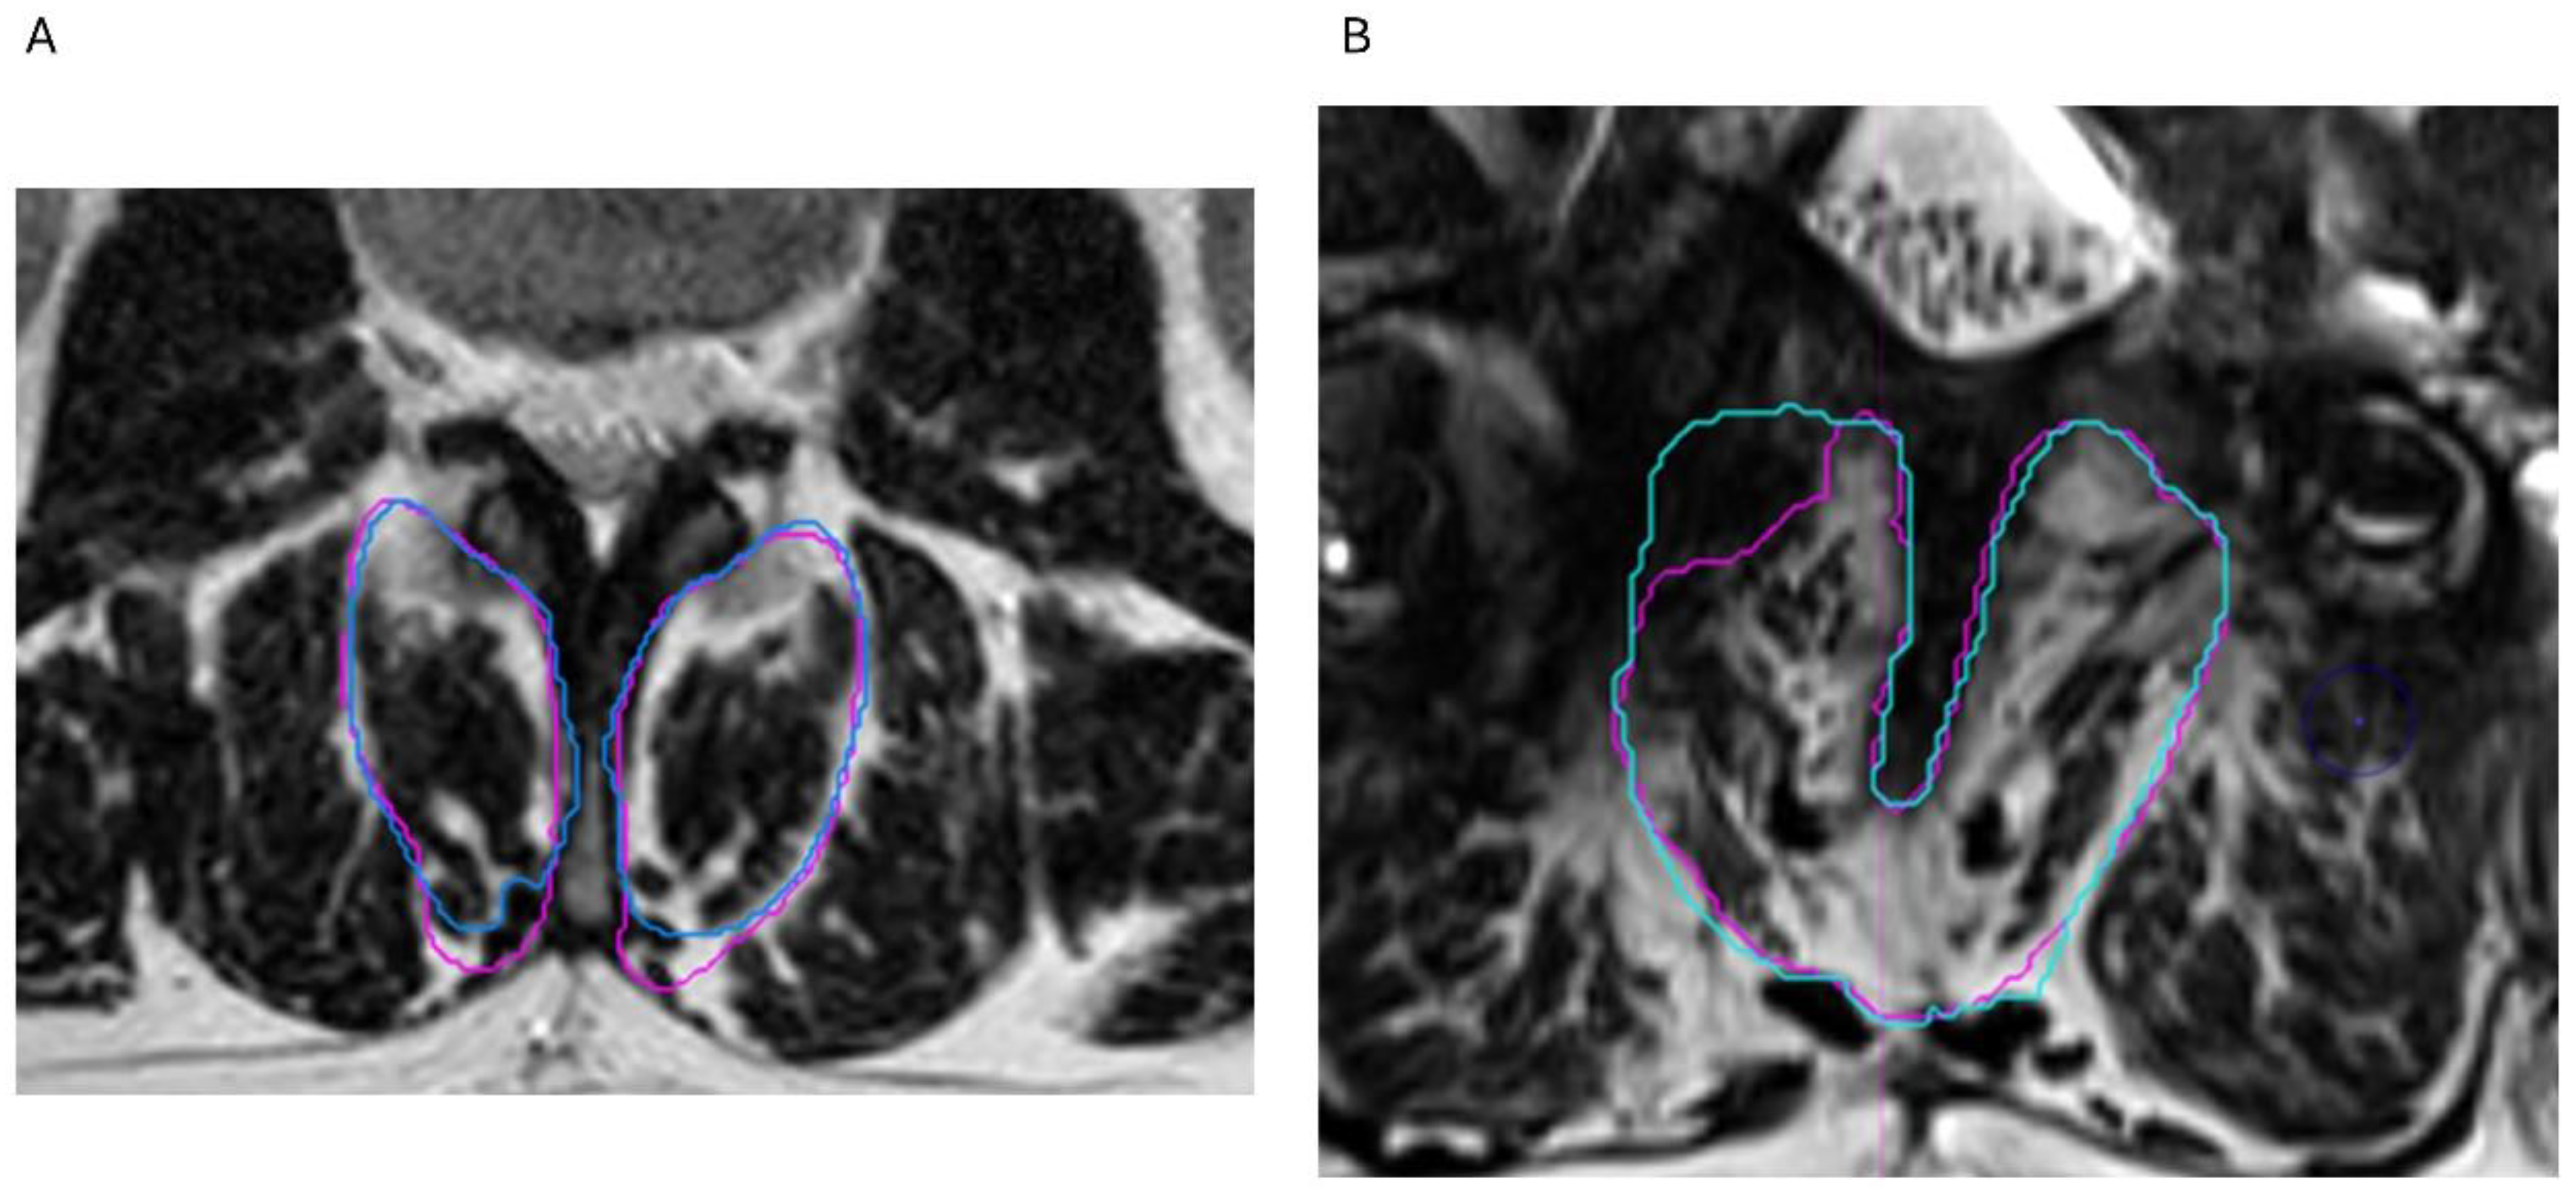

2.3. Segmentation Composition Analysis

3.3. Reliability Analysis

3.4. Fat Infiltration over Lumbar Levels